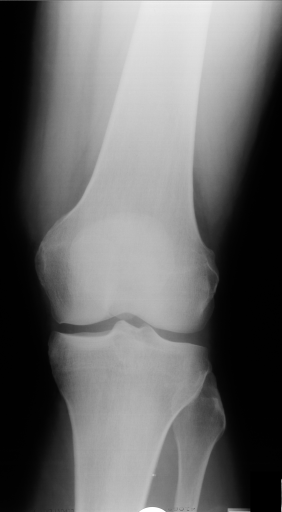

The IRMA dataset, supplied for the imageCLEF organization, had annotated codes were similar to domain expert knowledge [9, 12, 13, 14]. This database has been used by many researchers and is comprised of preset test and training portions, which enable direct comparisons of metrics. The IRMA codes (manually created by several clinicians) contains information on technical, biological and diagnostic traits of the image in a structured manner: TTTT-DDD-AAA-BBB. Each section is hierarchical meaning there is a least significant bit and most significant digit (Table 1). Sample IRMA images are depicted in Fig. 1.